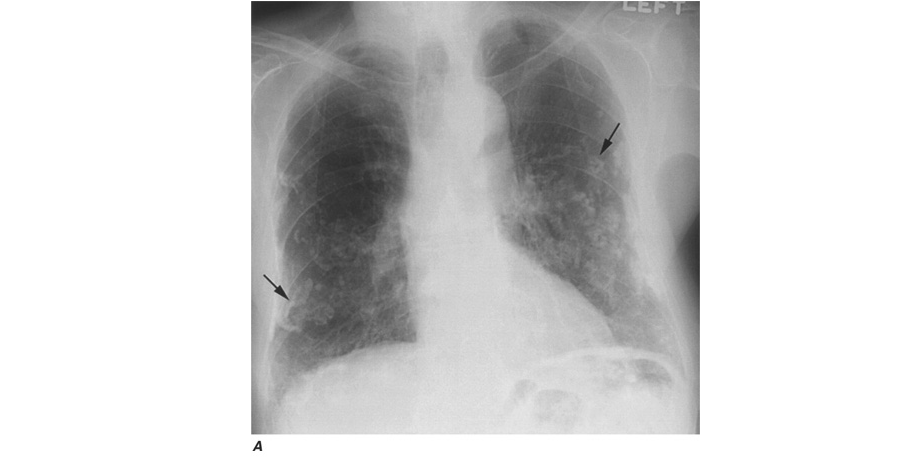

The chest radiograph can be used to detect the pulmonary manifestations of asbestos exposure. Past exposure is specifically indicated by pleural plaques, which are characterized by either thickening or calcification along the parietal pleura, particularly along the lower lung fields, the diaphragm, and the cardiac border. Without additional manifestations, pleural plaques imply only exposure, not pulmonary impairment. Benign pleural effusions also may occur. The fluid is typically a serous or bloody exudate. The effusion may be slowly progressive or may resolve spontaneously. Irregular or linear opacities, evidence of asbestosis that usually are first noted in the lower lung fields and spreading into the middle and upper lung fields, occur as the disease progresses. An indistinct heart border or a “ground-glass” appearance in the lung fields is seen in some cases. In cases in which the x-ray changes are less obvious, HRCT may show distinct changes of subpleural curvilinear lines 5–10 mm in length that appear to be parallel to the pleural surface (Fig. H-1).

Workers heavily exposed through sandblasting in confined spaces, tunneling through rock with a high quartz content (15–25%), or the manufacture of abrasive soaps may develop acute silicosis with as little as 10 months of exposure. The clinical and pathologic features of acute silicosis are similar to those of pulmonary alveolar proteinosis . The chest radiograph may show profuse miliary infiltration or consolidation, and there is a characteristic HRCT pattern known as “crazy paving” (Fig. H-2). The disease may be quite severe and progressive despite the discontinuation of exposure. Whole-lung lavage may provide symptomatic relief and slow the progression.